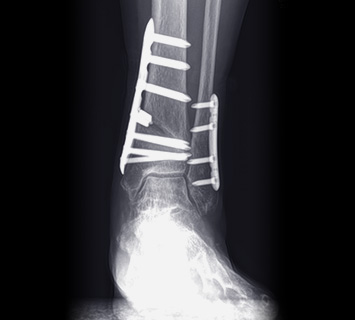

수술 전 / 수술 후

• 수술적치료 MICA수술

2mm정도의 미세 절개를 통해 주변 조직을 손상시키지 않고

뼈를 절골해 휘어진 발가락을 교정하는 수술